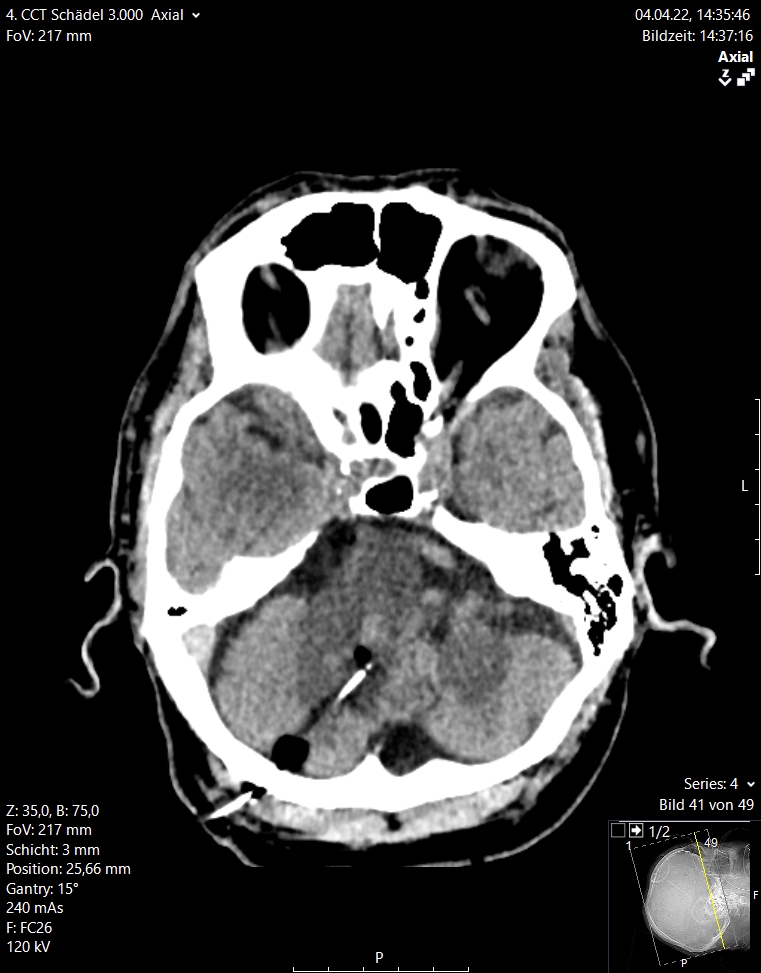

Περισσότερες λεπτομέρειες για τις ενδοεγκεφαλικές αιμορραγίες μπορείτε να διαβάσετε στο αντίστοιχο ενότητα στις παθήσεις (ενδοεγκεφαλικές αιμορραγίες)

Εδώ θέλουμε να τονίσουμε ότι σήμερα είναι δυνατό να αφαιρεθεί μια τέτοια αιμορραγία μόνο μέσω ενός ελάχιστα επεμβατικού ενδοσκοπικού χειρουργείου διάρκειας 20 με 30 λεπτών αντί για τα παραδοσιακά χειρουργεία στα οποία γινόταν μεγάλες κρανιοτομές. Στις εικόνες 12 και 13 απεικονίζονται οι προεγχειρητικές και μετεγχειρητικές εικόνες από δύο ασθενείς με ενδοεγκεφαλική αιμορραγία. Αυτές αφαιρέθηκαν ενδοσκοπικά μέσω μιας απλής κρανιοανάρτησης (1 εκ.)